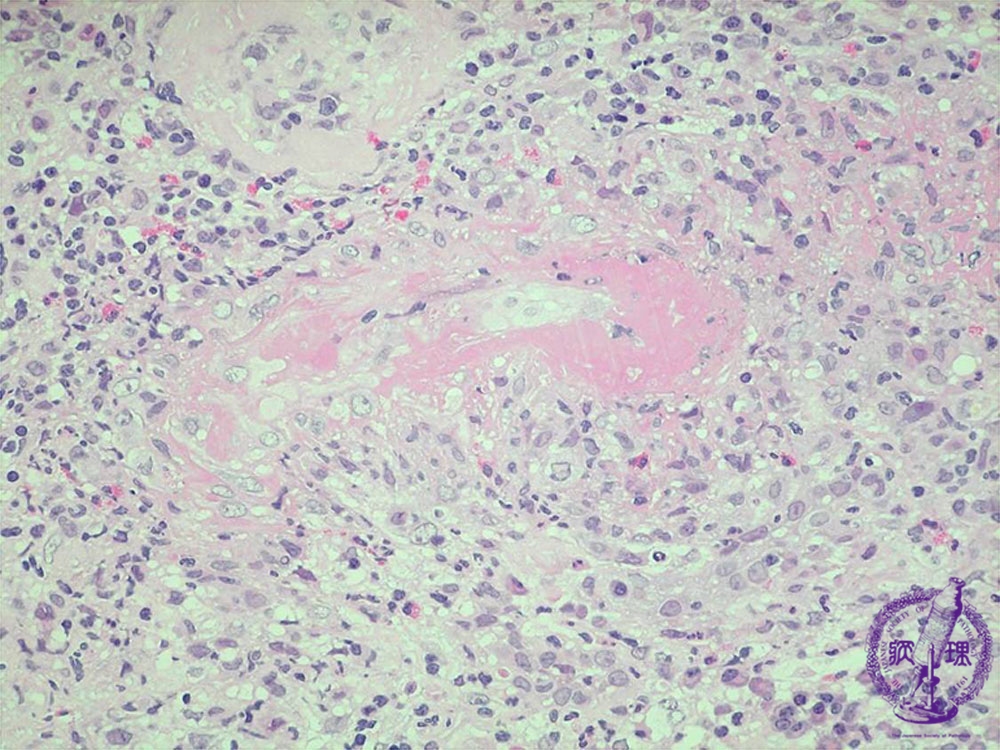

- ★(5)Crescent-forming glomerulonephritis

Microscopic findings ( HE, high power view):ANCA-related glomerulonephritis. There is interlobular artery vasculitis comprising fibrinoid degeneration, necrosis and destruction of the vascular wall (red dotted line = necrosis, red arrows = arterial wall).